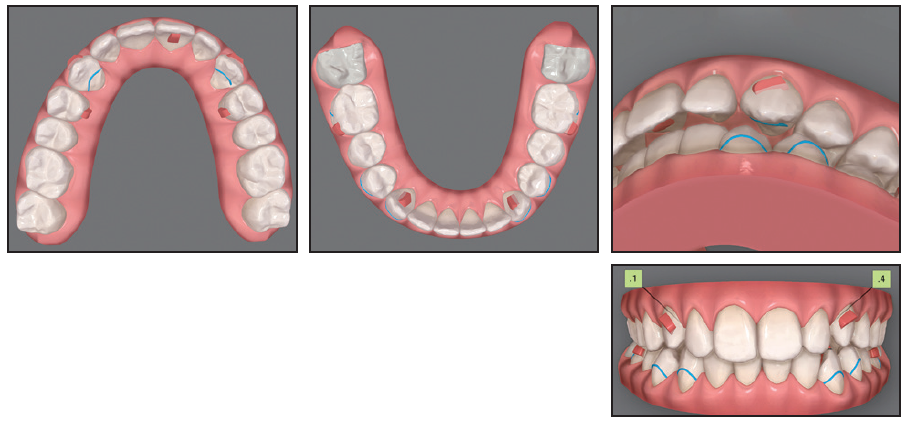

Case 1: Applying an Extrusive Traction Force

A 22-year-old female was referred by her general dentist for treatment of retained upper deciduous canines (Fig. 1A). She had a mildly convex soft-tissue profile, excessive lower anterior facial height, and an obtuse nasolabial angle. The smile arc was consonant, with 90% gingival display, but some lip incompetence was noted. The lower midline was deviated to the left of the facial midline. The overjet was 4mm, and the overbite less than 1mm. Mild Class II molar relationships were present on both sides.

Fig. 1 Case 1. 22-year-old female patient with bilaterally impacted upper canines before treatment (continued in next image).

The panoramic radiograph showed that both upper canines were impacted and slightly overlapping the roots of the lateral incisors. Cone-beam computed tomography (CBCT) evaluation revealed a palatal position of the left canine and a mid-crestal position of the right canine (Fig. 1B).

Fig. 1 (cont.) Case 1. 22-year-old female patient with bilaterally impacted upper canines before treatment.